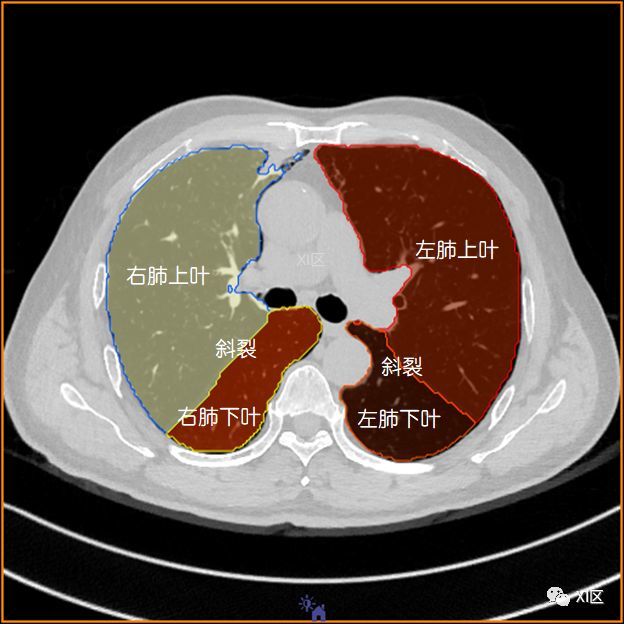

右肺上叶和下叶,左肺下叶

左肺借斜裂成上,下两叶;右肺借斜裂和水平裂成上,中和下叶三叶.